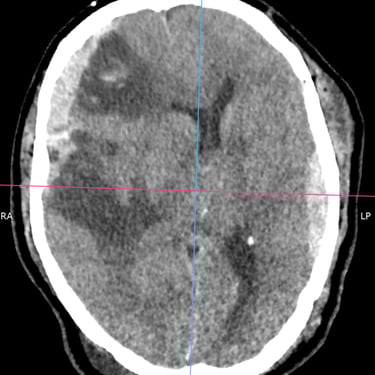

TEC Severo: Craneotomía Descompresiva Hemisférica y Evacuación de Hematoma Extradural

El traumatismo encéfalo craneano (TEC) severo es una emergencia neurológica que puede comprometer rápidamente la vida del paciente. Cuando existe edema cerebral difuso y hematomas asociados, el tratamiento quirúrgico oportuno es fundamental. La craneotomía descompresiva hemisférica derecha permite reducir la presión intracraneal y prevenir daño cerebral secundario, mientras que la craneotomía temporal izquierda con evacuación de hematoma extradural (HED) elimina el efecto de masa local. Este abordaje combinado busca preservar la perfusión cerebral, estabilizar al paciente y mejorar el pronóstico neurológico en situaciones críticas.